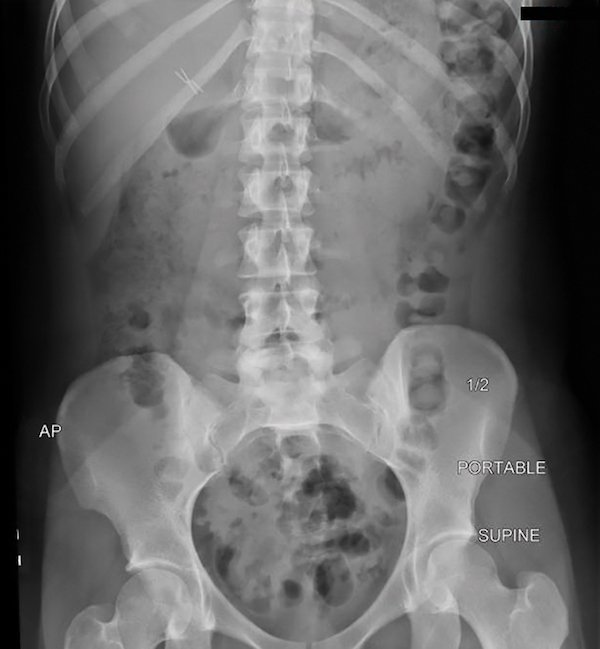

A 24-year-old woman with a history of newly diagnosed cystic fibrosis and pancreatic insufficiency was admitted for abdominal pain. Three days prior to admission, the patient woke up with periumbilical abdominal pain, nausea, and vomiting. She is afebrile. Physical exam is notable for positive bowel sounds and abdominal distention with diffuse mild tenderness, but without rebound or guarding. She had been having regular bowel movements prior to this admission but had noted some epigastric pain, bloating, and gas. She reports a prior admission with constipation but attributes that episode to being related to narcotic use in a postsurgery period. She recently tried polyethylene glycol without success. Abdominal plain film is shown in the figure. Which of the following is the most likely diagnosis?

B. Distal intestinal obstruction syndrome (DIOS)